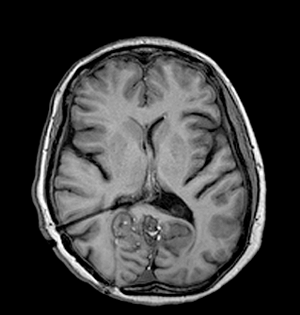

An MRI scan of the head and cervical spine revealed a large midline cerebellar tumor (5 x 5.7 x 6.9 cm) with heterogenous signal characteristics; there was chemical shift artifact indicating the presence of fat as well as evidence of previous rupture and diffuse subarachnoid / intraventricular dissemination of the fat (Figure 1). The tumor was exerting mass effect on the brainstem and causing mild obstructive triventriculomegaly.

Click below to enlarge

Figure 1: Sagittal T1-weighted MRI scan showing cerebellar tumor and intraventricular fat..